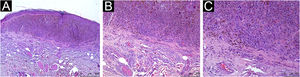

All assessed patients had TII, with different qualitative and quantitative classifications, with moderate to marked TII being present in 54.5% of the CM and 68% of the CNM tumors. For the crude data, an Odds Ratio (OR) of 0.57 (95% CI 0.18‒1.8; p = 0.338) was obtained (Table 2). The multivariate analysis with adjustments for Breslow thickness, sex and age at diagnosis of melanoma was applied, and the presence of moderate to marked TII showed an OR of 0.68 (95% CI 0.13‒3.99; p = 0.669; Table 2). Figs. 1, 2 and 3 show histopathological images of mild, moderate and marked TII in patients with TPCM.